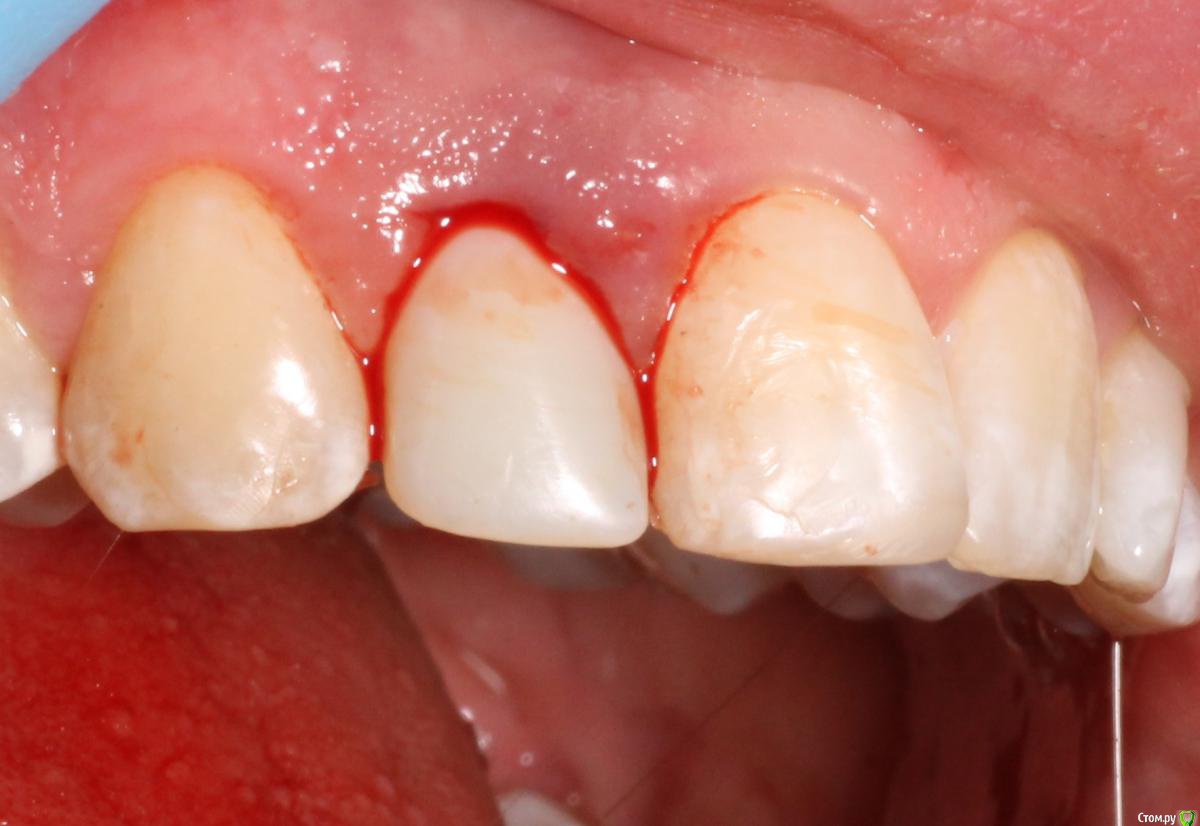

MenshikovDV Опубликовано 2 апреля, 2015 Поделиться Опубликовано 2 апреля, 2015 (изменено) Зуб 1.2 отлом коронковой части зуба, на период ожидания приема у хирурга и ортопеда (2 дня) приклеен к соседям. Вся процедура в одно посещение. Где-то часа два. Я ортопед, хирургия не моя, фото мои Изменено 2 апреля, 2015 пользователем MenshikovDV 19 Ссылка на комментарий

Aquarius Опубликовано 5 апреля, 2015 Поделиться Опубликовано 5 апреля, 2015 в такую дыру лучше что-нибудь кинуть, имхо. Ссылка на комментарий

Alexey Doc Опубликовано 5 апреля, 2015 Поделиться Опубликовано 5 апреля, 2015 Класс! Аккуратно сработали!Единственно, думаю что аугментации была бы желательна. Ссылка на комментарий